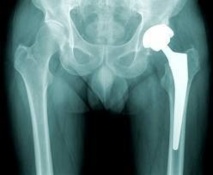

PARIS, 04 mai 2013 (AFP) - Le fabricant des prothèses de hanche, non conformes à la réglementation administrative, Ceraver, a souligné samedi dans un communiqué qu'"aucune prothèse défectueuse n'a été posée" sur des patients qu'il souhaitait "rassurer".

La société, qui s'est vue reprocher d'avoir fournie des prothèses de hanche non conformes, dont 650 patients sont porteurs en France, "souhaite rassurer les patients et les chirurgiens" en rappelant qu'il s'agit d'une "non-conformité administrative".

Tout en notant les "propos rassurants" de l'agence du médicament (ANSM) et de la ministre de la Santé à ce sujet, Ceraver a affirmé qu'aucune prothèse défectueuse n'a été fabriquée ou livrée et a fortiori "aucune prothèse défectueuse n'a été posée" sur des patients.

Néanmoins, l'agence sanitaire a demandé aux chirurgiens orthopédistes ayant implanté ces prothèses de revoir leurs patients pour faire un bilan clinique et radiologique.